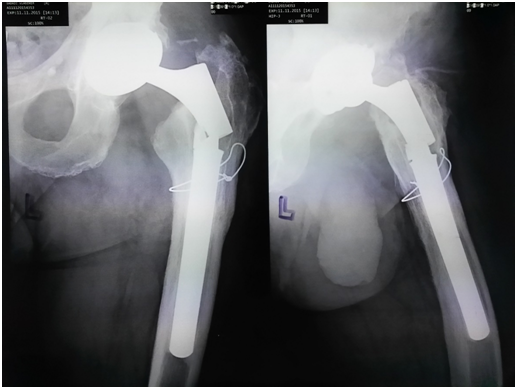

The patient is a 61-year-old, Caucasian man measuring 180cm in height and 100kg in weight, with body mass index of 30.86 (BMI). He was diagnosed with a bilateral hip osteoarthritis and admitted to our Department in November 2009 when total hip arthroplasty (Lima SPH-ST/C2, Lima International, Udine, Italy) of the right hip was performed. Subsequent total hip arthroplasty (Lima SPH-ST/C2, Lima International, Udine, Italy) of the left hip was performed in November 2010 (Figure 1). The patient underwent regular ambulatory controls with clinical and radiology examinations. Because of the aseptic loosening of femoral stem (stem subsidence) a revision surgery was made in February 2014. Revision femoral stem was implanted (Lima revision, Lima International, Udine, Italy) (Figure 2) using trans femoral approach according to Wagner in the lateral decubitus position.9 Femoral component was a cementless modular porous-coated stem made of titanium alloy with distal anchoring (tapered, fluted). Size of femoral stem was 22x140mm with the proximal part length of 70mm (total stem length 210mm). Postoperative course was without complications. Patient felt a sudden sharp pain in his left hip while walking in October 2015, 20 months after the revision procedure. Limping and the pain in left hip were increasing daily. He presented to our Department with the leg held in the external rotation and with decreased movements in hip joint. Plain radiograph showed a fracture of the revision femoral component of the left hip (Figure 3). The patient underwent a planned revision surgery procedure. Trans femoral approach according to Wagner was used again.9 Fracture was found at a junction between proximal and distal part of the stem (Figures 4 & 5). Extraction of the distal part of the stem was performed using technique developed at our Department.10 Proximal part is easy to extract without any complications. Problem is with distal part that is firmly fixed in the bone. It was removed with a special longitudinal osteotomy through the anterior cortex extending distally for 15cm. It was then followed by a transversal osteotomy 2cm below the tip of the femoral stump to allow enough space for two locking pliers. Simultaneously using a lamina spreader on the distal part, the broken stem was extracted while hammering on two locking pliers. Cementless revision femoral stem was implanted in a standard manner (Figure 6).

Figure 1 Plain radiograph of primary bilateral total hip endoprosthesis.

Figure 2 Plain radiograph of revison modular total hip endoprosthesis.